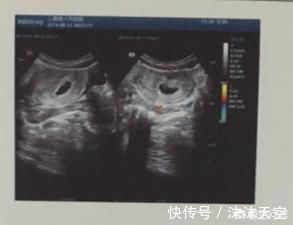

二、查看孕囊的情况

孕早期需要在B超下查看孕囊的位置、大小、形态,以排除空孕囊、假孕囊。也就是说看见孕囊了不代表就正常怀孕了,也可能是怀了个假孕。

四、确认胚胎个数

确认怀的是单胎还是双胎、多胎。